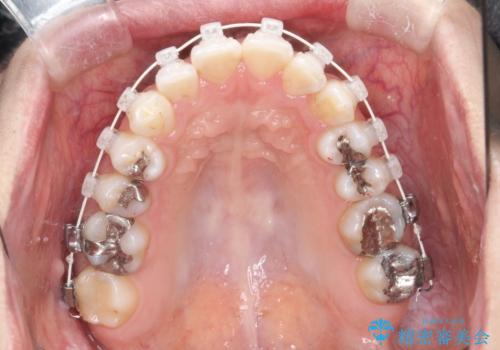

【ワイヤー矯正】前歯の凸凹を非抜歯で治療

- 前歯の凸凹を主訴に来院されました。

側方拡大にてスペースを作ることにより綺麗に前歯を並べることができました。

前歯の凸凹がある場合は治療計画を立てる上でスペースをどのように作るかが重要になります。

今回の場合は主に側方拡大でスペースの確保を行いました。